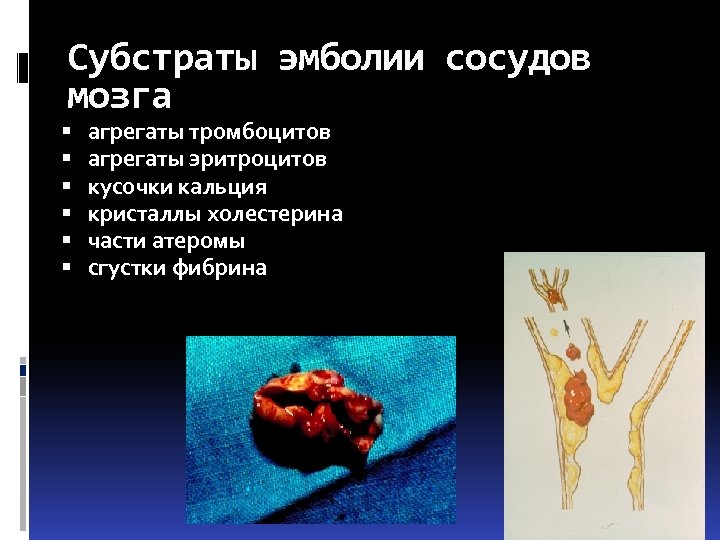

Субстраты эмболии сосудов мозга агрегаты тромбоцитов агрегаты эритроцитов кусочки кальция кристаллы холестерина части атеромы сгустки фибрина

Субстраты эмболии сосудов мозга агрегаты тромбоцитов агрегаты эритроцитов кусочки кальция кристаллы холестерина части атеромы сгустки фибрина